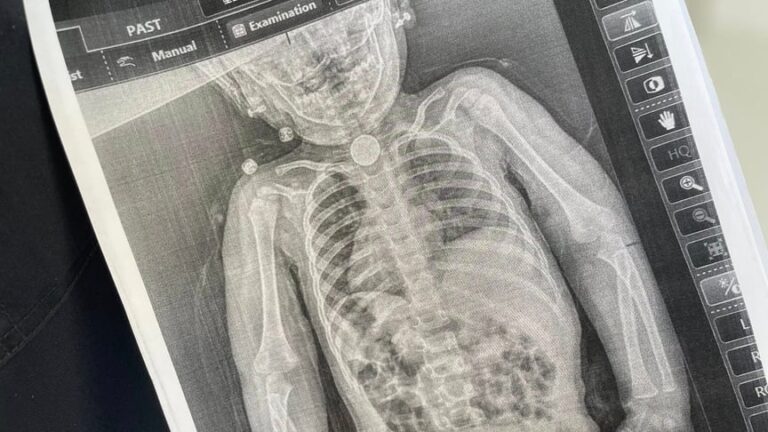

Наше здоров’я та врода — це головний ресурс, який допомагає відчувати себе впевнено кожного дня. Редакція «Україночки» підготувала для вас корисний матеріал про те, як уникнути небезпеки при вживанні дикорослих рослин, адже необережність може призвести до трагічних наслідків. Нещодавня трагічна…